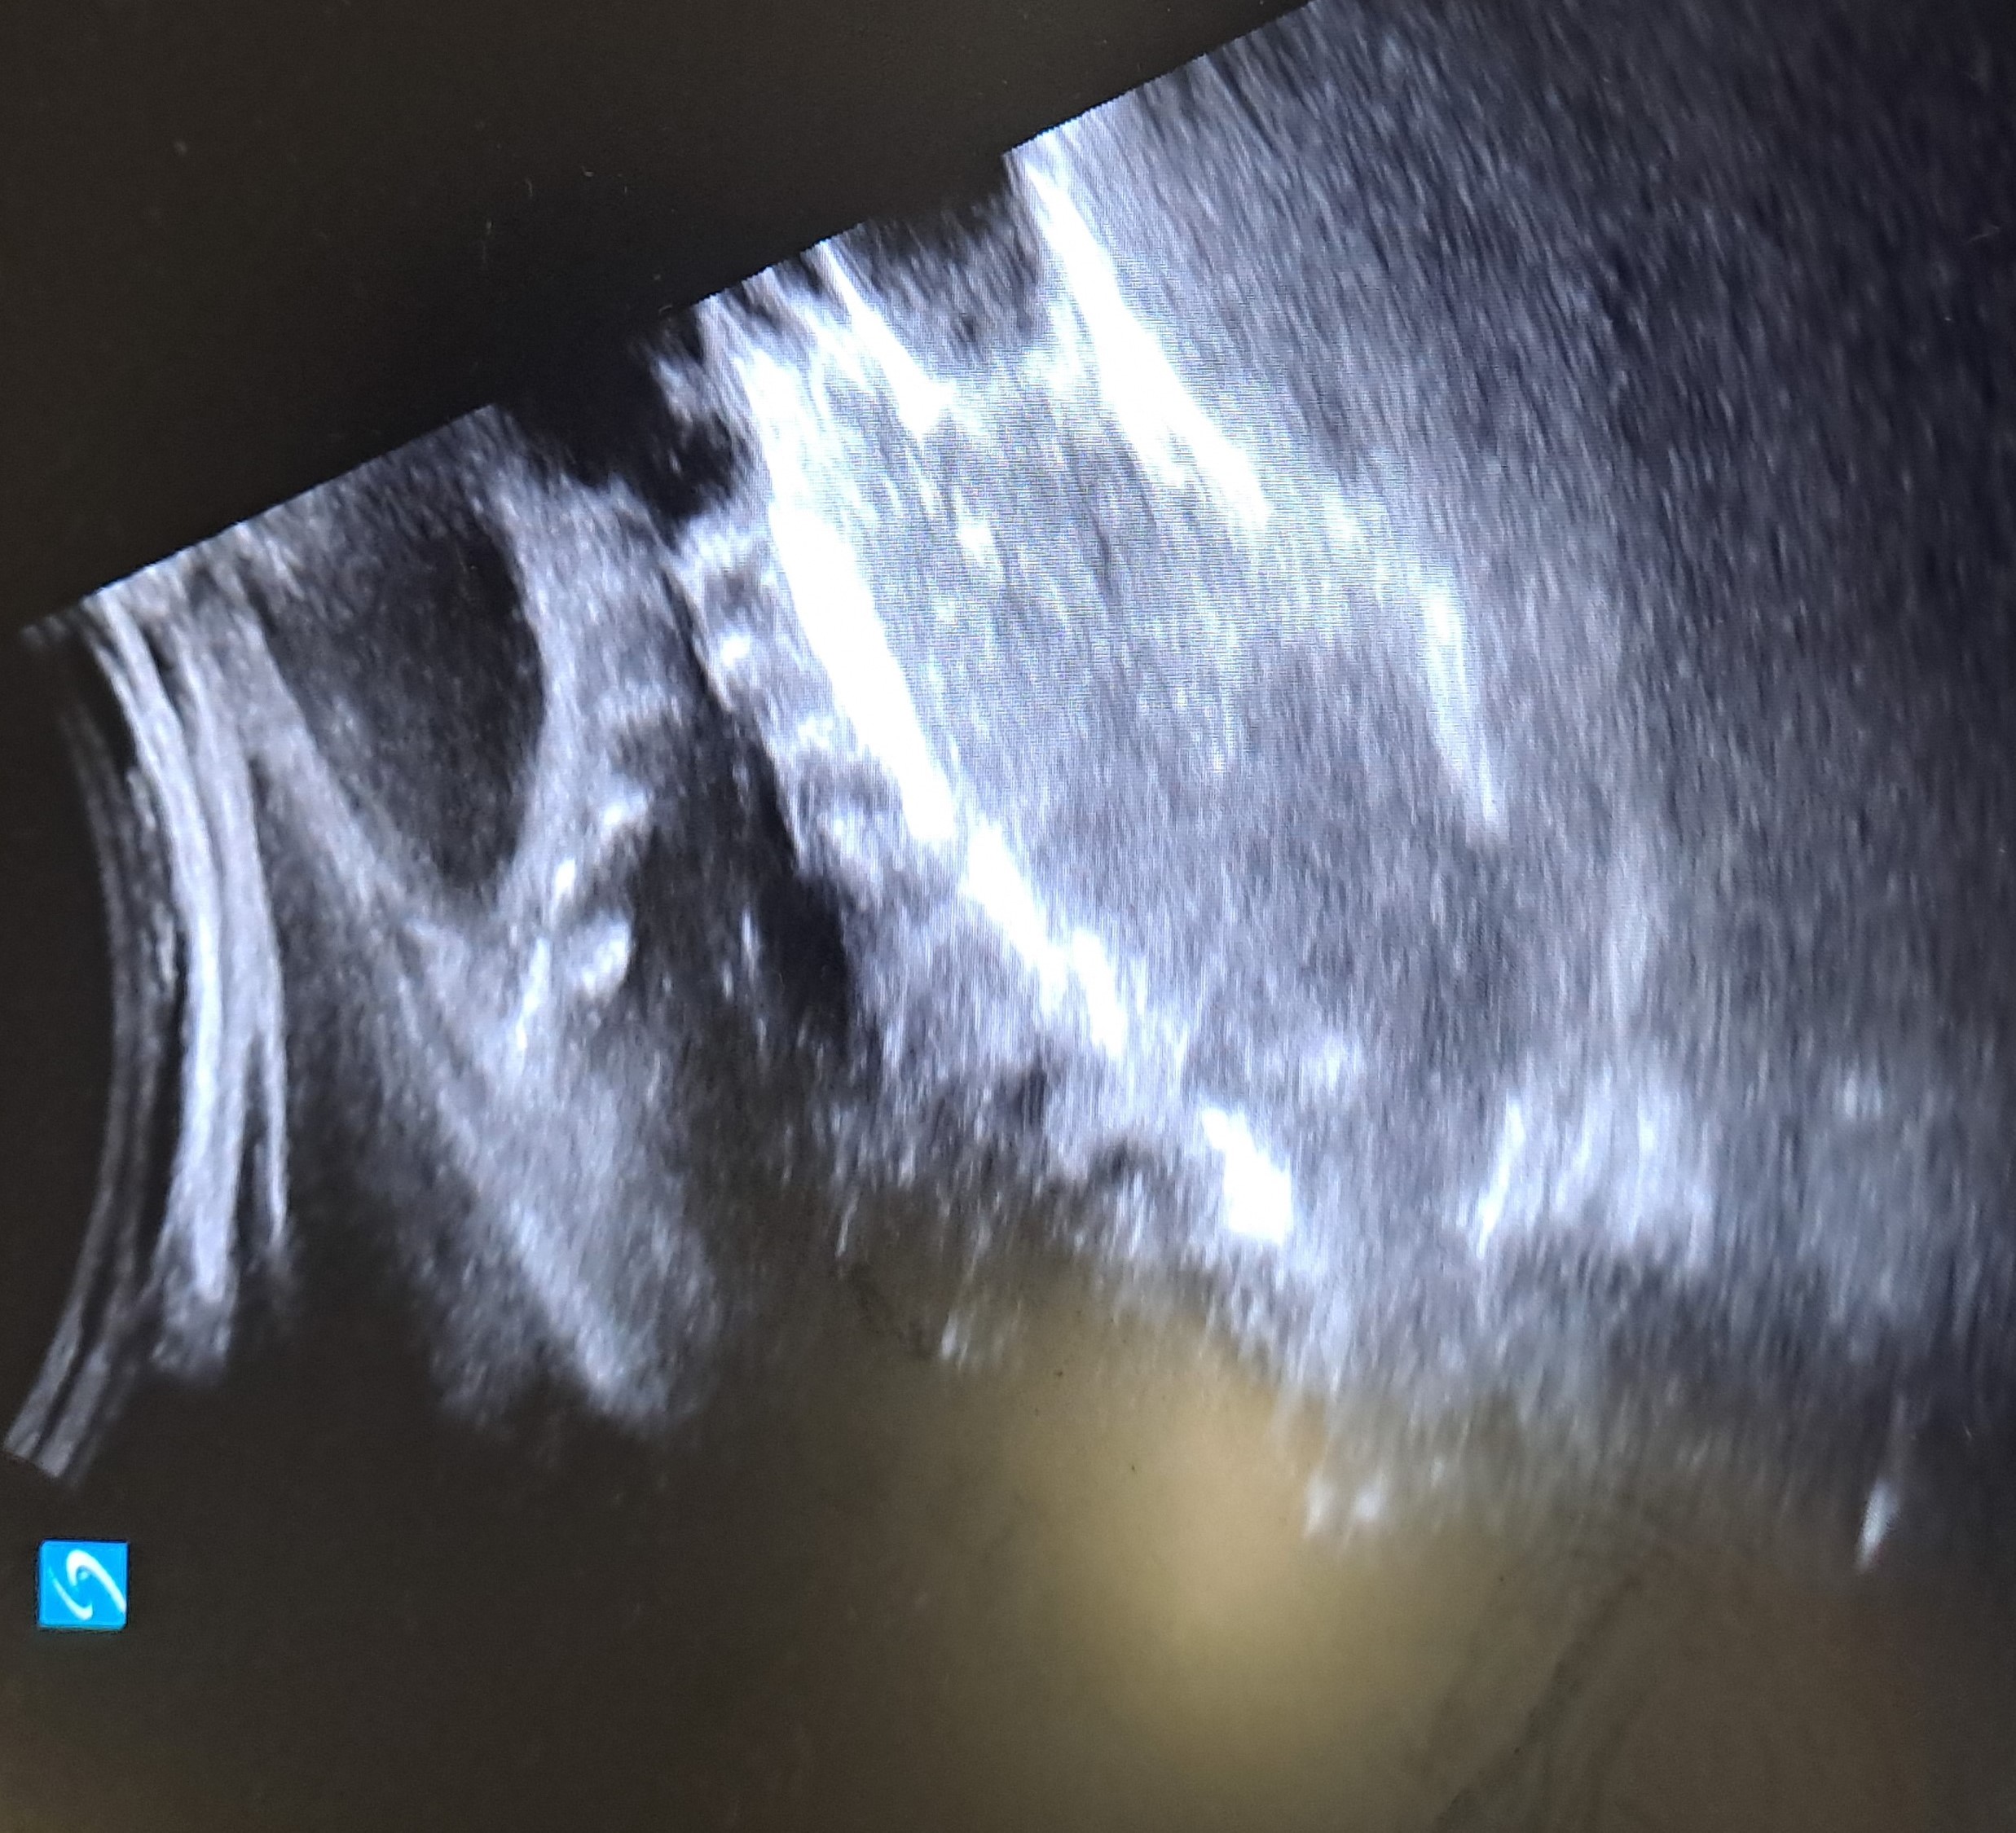

Se realiza ecografía clínica objetivando asas intestinales dilatadas con engrosamiento de paredes y ausencia de movimiento de asas intestinales.

La ecografía clínica permitió en este caso valorar a un paciente que presentaba un abdomen agudo de cara a dirigir las pruebas complementarias.